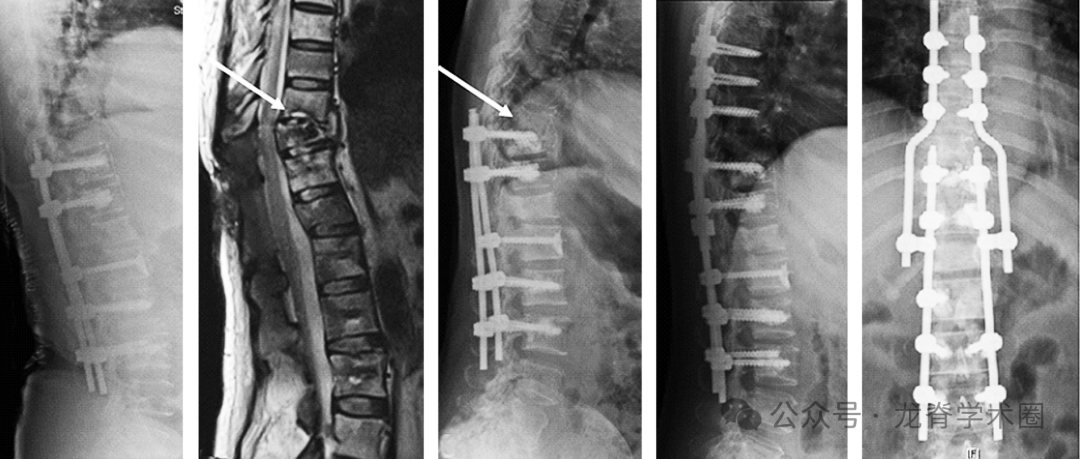

2005年至2015年共有288例患者接受了MSTS。42例患者被排除在外,因为他们在手术后30天内死亡,或者他们的MSTS没有使用内固定。因此,最终包括246例患者。5.7%(14/246)的受试者出现SF,其中71%(10/14)的患者进行了翻修手术。所有的SF都是Construct failure,然而,没有SF是绝对意义的Implant failure。16%(41/246)的患者在研究结束时表现出无临床症状的Implant failure/Construct failure的影像学证据。

患者平均年龄58.8岁,127名男性(51.6%)和119名女性(48.4%)。常见的肿瘤类型为肺癌(27.6%)、乳腺癌(16.7%)、血液系统肿瘤(12.9%)、肝癌/胃癌/肠癌(10.9%)、肾癌(9.3%)、前列腺癌(8.9%)。大多数(66.3%)病变为溶骨性病变。中位生存期为13.4个月。SF患者的中位生存期为21个月。从手术到SF的平均为12.8±17.7个月,到内固定失败的中位时间为5个月。SF患者中,顽固性疼占78.5%(11/14);新发神经功能障碍占50%(7/14);假体移位占14.2%(2/14);继发性伤口裂开占7.1%(1/14)。64.3%为SINS评分7-12分, 35.7%)为SINS评分>12分。13/14(92.8%)的内固定跨越交界区。49例(19.9%)采用MIS手术,194例(78.9%)采用开放手术。对SF患者手术类型进行亚组分析,4例(28.6%)患者行MIS, 10例(71.4%)患者行开放手术。手术类型与SF无明显相关性。

单因素和多因素竞争风险回归模型显示,术前活动状态(ECOG≤2)是SF的重要危险因素,死亡是一个竞争事件。术前SF患者11例(78.5%)可以走动,3例(21.4%)不能走动。使用助步器的患者发生种SF的风险高出7倍。此外,由于所有SF患者SINS>7分,因此SINS>7分是一个危险因素。同样,SINS>12分也具有显著性。两组间的亚组分析显示,SINS评分>12的SF发生率为11.9%(5/42),高于SINS评分为7-12分,5%(9/178)。这一差异具有统计学意义。跨越交界区是另一个危险因素,93%(13/14)的SF患者跨越交界区。

结论:MSTS患者SF的发生率较低(5.7%)。术前使用助步器患者的SF风险比不使用助步器的高7倍。术前SINS>7分和内固定跨越交界区与SF相关。大多数内固定失败发生在假体-骨界面。